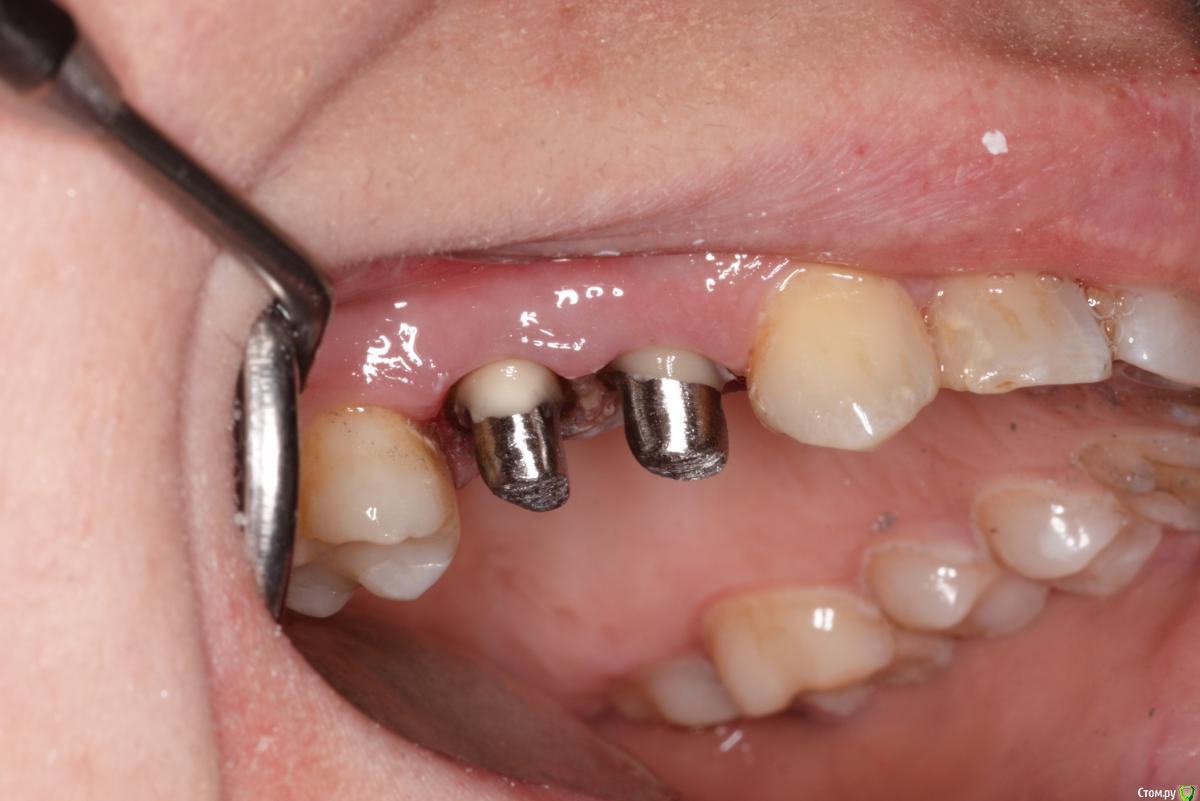

skeettrap Опубликовано 5 июля, 2016 Поделиться Опубликовано 5 июля, 2016 Стандартная ситуация : коллега попросила сделать родственнице (мужа) за неделю - во время краткосрочного визита из Израиля.Исходная ситуация 14,15 сильно разрушены с временными пломбами и наплывшей десной(фото не сделал).На первом этапе сделаны культевые вкладки прямым методом (десну подрезал бором). Постановка вкладок на следующий день, изготовление временных коронок, снятие слепков. Через 2 дня - фиксация. Ссылка на комментарий